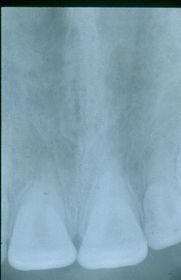

Radiografía acortada Causada por mucha angulación vertical. Las raíces se ven acortadas en la imagen.